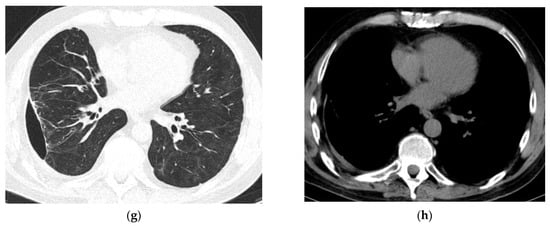

Figure 4.

Radiologic evolution of case 2: Initial axial and coronal chest CT scans with left lower lobe abscess prior to rupture into the pleural cavity, extended bilateral lung infiltrates, and consolidations (a,b). Inserted percutaneous ICD used for both pleural lavage and drainage, trapped lung with small fluid retention (a), diffuse pulmonary infiltrates in both lung fields (c,d), and small left pulmonary cavitary lesions (d). Chest CT scans follow-up reveals intracavitary Pezzer catheter (used instead of Foley catheter due to a large soft tissue defect secondary to chest tube infection) and left-sided pyopneumothorax with mixed density fluid after lavage, ground-glass opacities (GGO) and left pulmonary consolidations areas (e,f). Six months follow-up shows complete closure of pleural and pulmonary cavities, and resolution of pulmonary infiltrates except for two small fibrotic areas (g,h).